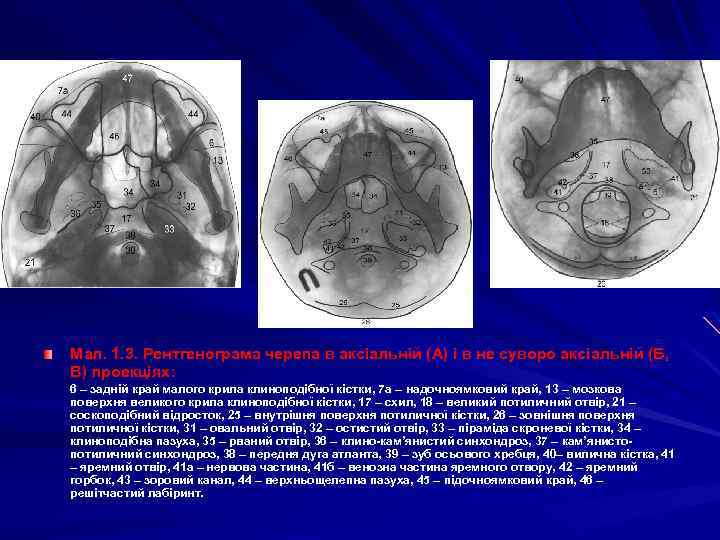

Мал. 1. 3. Рентгенограма черепа в аксіальній (А) і в не суворо аксіальній (Б, В) проекціях: 6 – задній край малого крила клиноподібної кістки, 7 а – надочноямковий край, 13 – мозкова поверхня великого крила клиноподібної кістки, 17 – схил, 18 – великий потиличний отвір, 21 – соскоподібний відросток, 25 – внутрішня поверхня потиличної кістки, 26 – зовнішня поверхня потиличної кістки, 31 – овальний отвір, 32 – остистий отвір, 33 – піраміда скроневої кістки, 34 – клиноподібна пазуха, 35 – рваний отвір, 36 – клино-кам’янистий синхондроз, 37 – кам’янистоклино-кам’ потиличний синхондроз, 38 – передня дуга атланта, 39 – зуб осьового хребця, 40– вилична кістка, 41 – яремний отвір, 41 а – нервова частина, 41 б – венозна частина яремного отвору, 42 – яремний горбок, 43 – зоровий канал, 44 – верхньощелепна пазуха, 45 – підочноямковий край, 46 – решітчастий лабіринт.